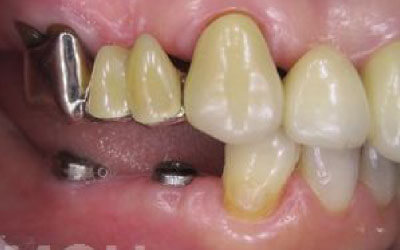

インプラント

ブリッジ

入れ歯

| 歯を削る | 削らない | 削る | 少しだけ削る |

| 周りの歯への 力の負担 |

負担をかけない | 非常に大きい | 大きい |

| 使用感 | 自分の歯に近い感覚 | 銀歯の場合は目立つ | 異物感を感じやすい |

ただインプラントは、人工歯根を通して骨が力を支えるので、残っている歯への負担が圧倒的に少ないのです。

しかしインプラント治療なら、前後の歯を削る必要も神経をとる必要もありません。歯の寿命を延ばす上でも、健康な歯をできるだけ削らないのはとても大切なことなのです。

インプラントだと固定式なので取り外す必要もなく煩わしさが圧倒的に少ないです。見た目も、他の人からはわからないケースがほとんどです。